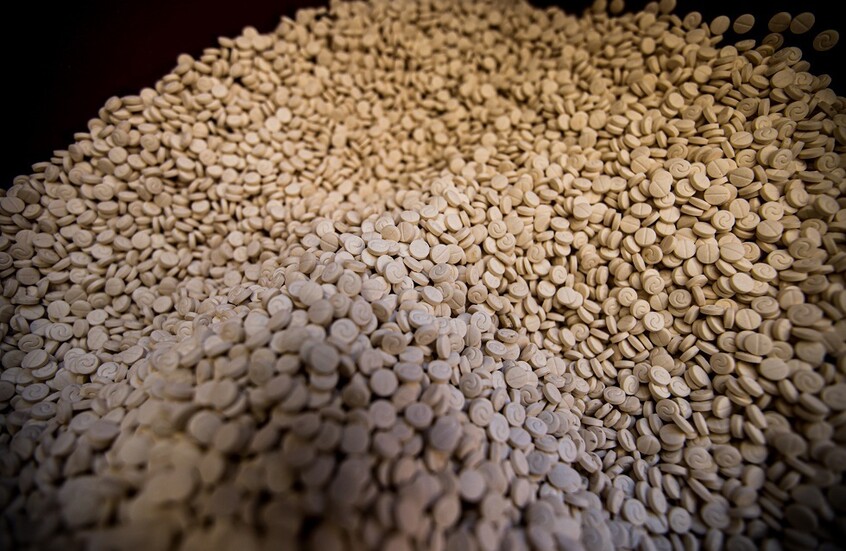

ويشار إلى أنه لا توجد علاجات لالتهاب الكبد الوبائي أ ولكن يمكن الحصول على لقاح إذا كان الشخص معرضا لخطر الإصابة بالمرض.

ويمكن تناول مسكنات الألم مثل الباراسيتامول أو الإيبوبروفين لتخفيف بعض الأعراض والحصول على قسط كبير من الراحة وتجنب الكحول وتناول وجبات صغيرة.